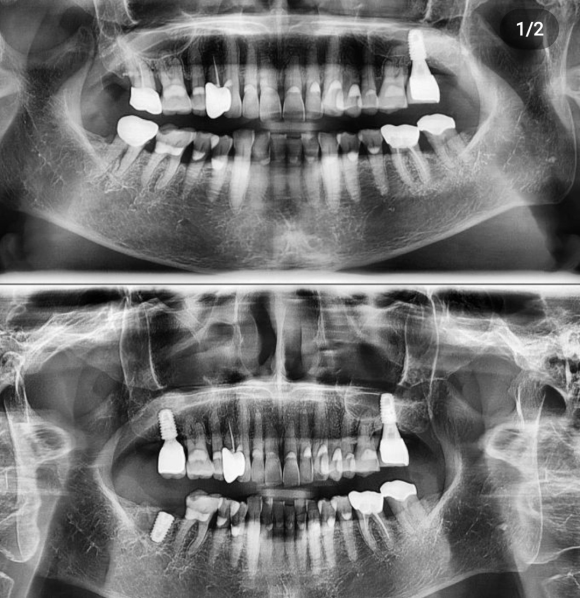

자연 치아를 보시면 머리 뿌리 경계부위 하얗게 떼워놓은 것이 보이는 것 처럼..

딱딱한 음식을 선호하시는 분의 치아 목부위가 전체적으로 파절이 되고

과중한 하중을 60년 세월을 감당한 치아가 수명을 다 하여

치아의 극심한 통증으로 치아를 발치하고 임플란트를 하게된 케이스 입니다.

치주인대가 쿠션 역할을 해주는 자연치아와 달리

뼈와 직접적인 결합으로 유착하는 임플란트의 특성상

딱딱한 음식에 매우 취약하기 때문에

성공적인 임플란트 수술과 함께 식단 관리까지 신경써야 하는 환자입니다.